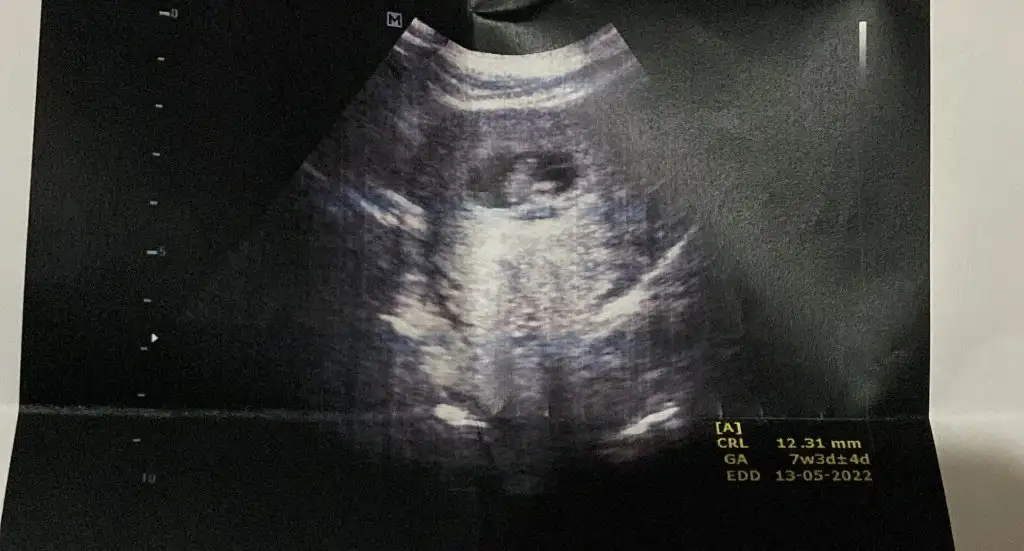

Canim benim 7. Haftamda var ilk ultrasonum yolluyorum sana5+6 yani 6.haftamdaki usg’de belli oldu teori, senin de varsa 6-7.haftaya kadar bakalım beraber tutacak mı

Canim benim 7. Haftamda var ilk ultrasonum yolluyorum sana

Bu arada bu karın ultrasonum5+6 yani 6.haftamdaki usg’de belli oldu teori, senin de varsa 6-7.haftaya kadar bakalım beraber tutacak mı

Sanki sola daha yakın gibi canım, erkek gibi yani ne dersinCanim benim 7. Haftamda var ilk ultrasonum yolluyorum sana

Canim kesenin içinde nereye yakin oldugu onemli degil mi bu teoride ? Burada solda duruyor bence deSanki sola daha yakın gibi canım, erkek gibi yani ne dersin

Evet canım, kesede sola daha yakın geldi bana da, ve karındansa erkek demekmiş ya..Canim kesenin içinde nereye yakin oldugu onemli degil mi bu teoride ? Burada solda duruyor bence de